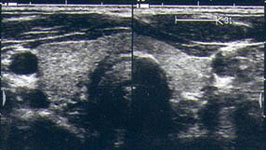

Die Sonographie mit hoch auflösenden Schallköpfen (7,5 bis 12,5 MHz mit Duplex) stellt heute bereits wenige Millimeter große Herdbefune präzise dar. Es existieren sonographische Kriterien, auf deren Basis, maligne Schilddrüsenknoten mit sehr hoher Sicherheit identifiziert werden können. Hierzu gehören unter anderem die Hypoechogenität, die unregelmäßige Randbegrenzung, Mikroverkalkungen sowie eine zentral verstärkte Vaskularisation.